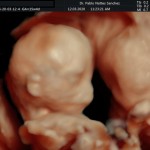

- De la edad gestacional (precisión en el cálculo del tiempo de embarazo).

- Crecimiento fetal.